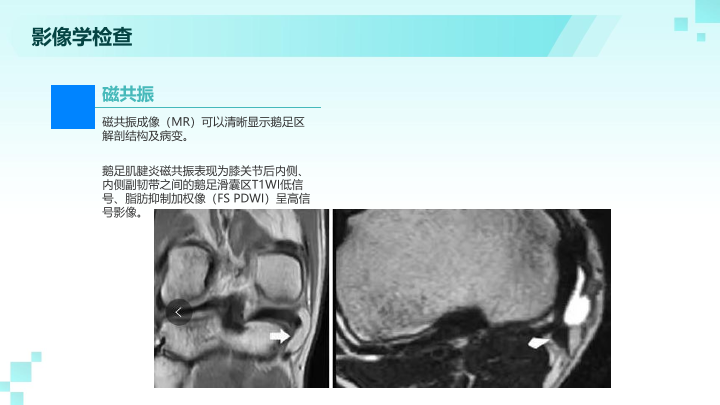

鹅足炎